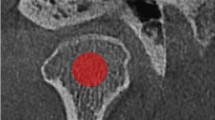

This retrospective study included 16 DM and age and sex matched 16 control patients (11 men, 5 women; mean age, 56.8 ± 14.4 years; range 31–78 years). Patients with Type I DM, prior history of taking bisphosphonates, osteoarthritis of the temporomandibular joint, and CT images with metal artifacts were excluded from this study. Bilateral mandibular condylar bone marrow was manually contoured on axial CT images. The presence or absence of DM is the primary predictor variable. Texture features of the region of interest was the outcome variable, that were analyzed using an open-access software, MaZda Ver.3.3. For each group, 20 features out of 279 parameters were selected with Fisher, probability of error and average correlation coefficient methods in MaZda. Bivariate statistics were computed with the Mann–Whitney U test and the P value was set at .05.